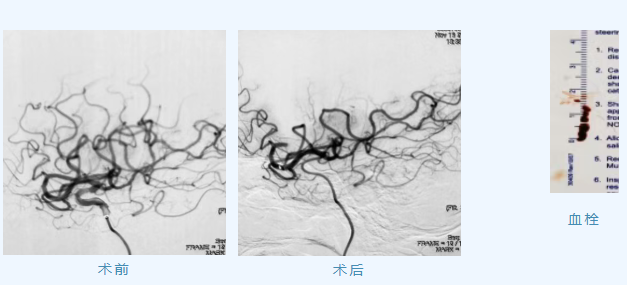

病例1:患者68岁女性,因“左侧肢体活动不灵2小时”急诊入院,急诊重症医学部团队完善颅脑CT检查,评估病情后及时给予静脉溶栓治疗,溶栓效果不佳,邀请神经内三科会诊,张松副主任立即查看患者,既往有高血压、冠心病、房颤病史,考虑为心源性栓塞,与患者家属沟通病情建议行急诊脑血管造影检查+必要时急诊取栓治疗,家属同意后,神经介入科主任王伟、神经内三科副主任张松带领神经介入团队行急诊脑血管造影检查,证实为右侧大脑中动脉上干闭塞,给予支架取栓,血流恢复通畅,术后返回EICU观察治疗,第三天转回普通病房,10天后患者康复出院。